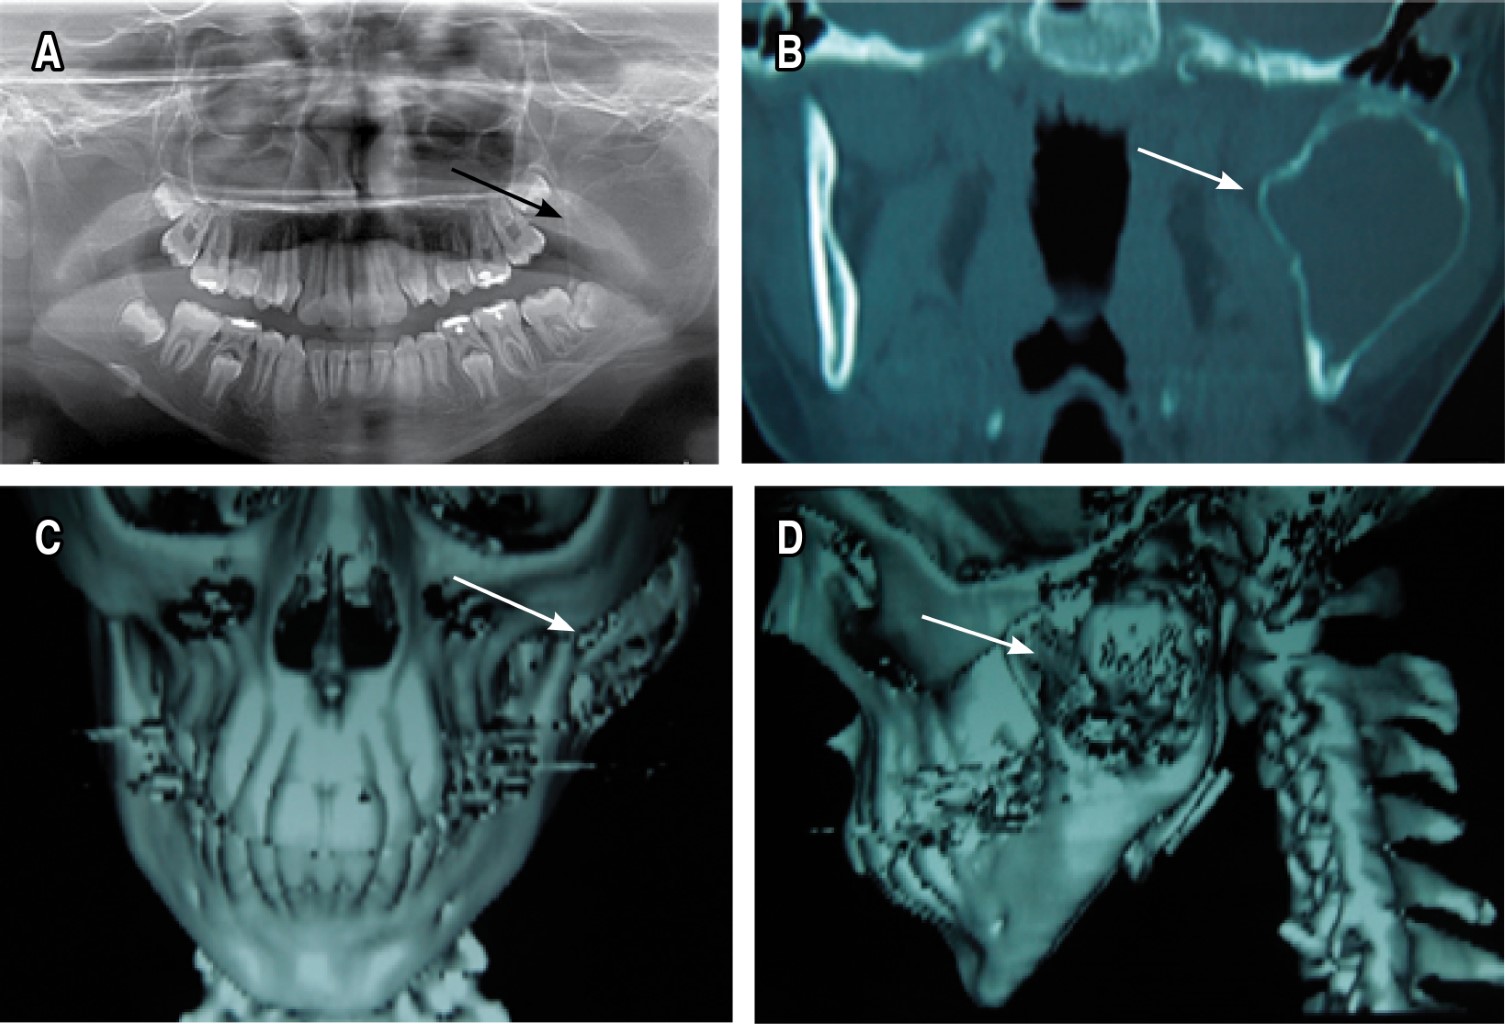

Introduction: simple bone cyst is a non-neoplastic, asymptomatic lesion, which is usually detected by radiographic finding. It is characterized by slow growth and non-expandable, which does not cause functional alteration. Presentation of the case: an 11-year-old female patient with a unicameral bone cyst that has atypical characteristics, at the level of the left mandibular ramus, with extension to the condyle and coronoid process, and with severe expansion of the bone tables. Treatment was surgical, by simple curettage. Two years after the treatment, there is no recurrence. Conclusions: diagnosis of cysts in the maxilla and mandible are common in oral and maxillofacial pathology, whose treatment is surgical.

Figure 2